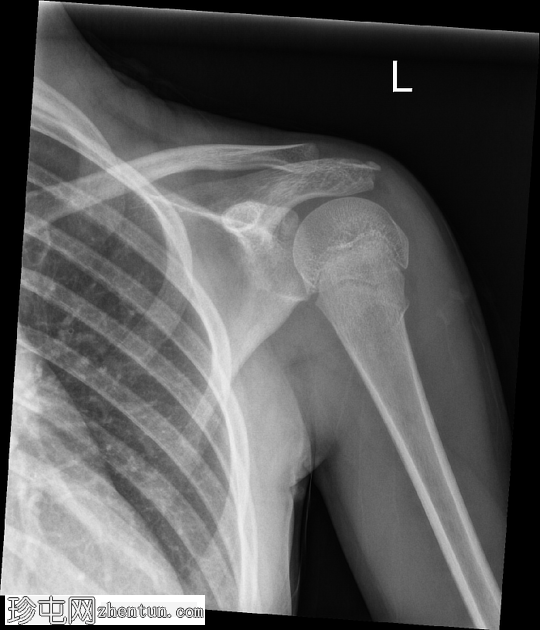

正位片

左侧肱骨近端干骺端可见环状骨折。皮质轮廓轻度不规则,呈环状弯曲,但无明显移位或成角。肱骨头与肩胛盂对位良好。